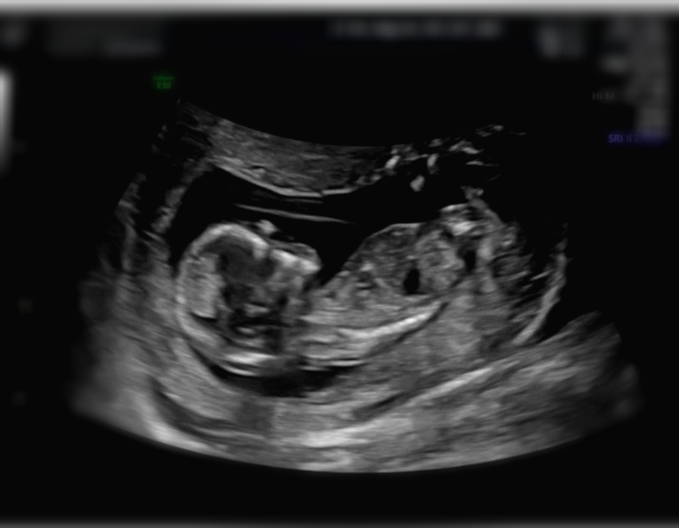

12주는 이제 정말 사람의 형태가 되어 있어서 너무너무 신기해요!!

옆모습을 봐도 이마, 콧대, 입술이 보이고, 목과 몸통도 나눠져있구요.

아니 쪼끄만 몸에 척추뼈도 선명히 보이고, 몸에 뼈들도 너무 선명히 엑스레이처럼 보이는게 정말 '아 내 배 안에 사람이 있구나' 하고 생각하게 되더라구요 ㅋㅋ

맨 마지막 사진처럼 12주에는 처음 입체초음파도 해주세요ㅎㅎ

임신 중 12주는 1차 기형아 검사를 하는 주수예요.

1차 기형아검사는 목 투명대와 콧대 등을 측정하고 검사하는데요.

12주가 넘어가면 아가가 커져서 목 투명대가 정확하지 않다고 해요.

목 투명대는 3mm가 넘어가면 두껍다고 판단을 하구요.

저희는 목 투명대가 목 둘레를 재는줄 알았는데 위 사진처럼 목 뒷 부분을 재는거더라구요? ㅋㅋ

1차 기형아 검사가 무슨 시험 준비하는 것처럼 너무너무 걱정됐는데 다행히 꼬미는 1.8mm로 통과했습니당~☺